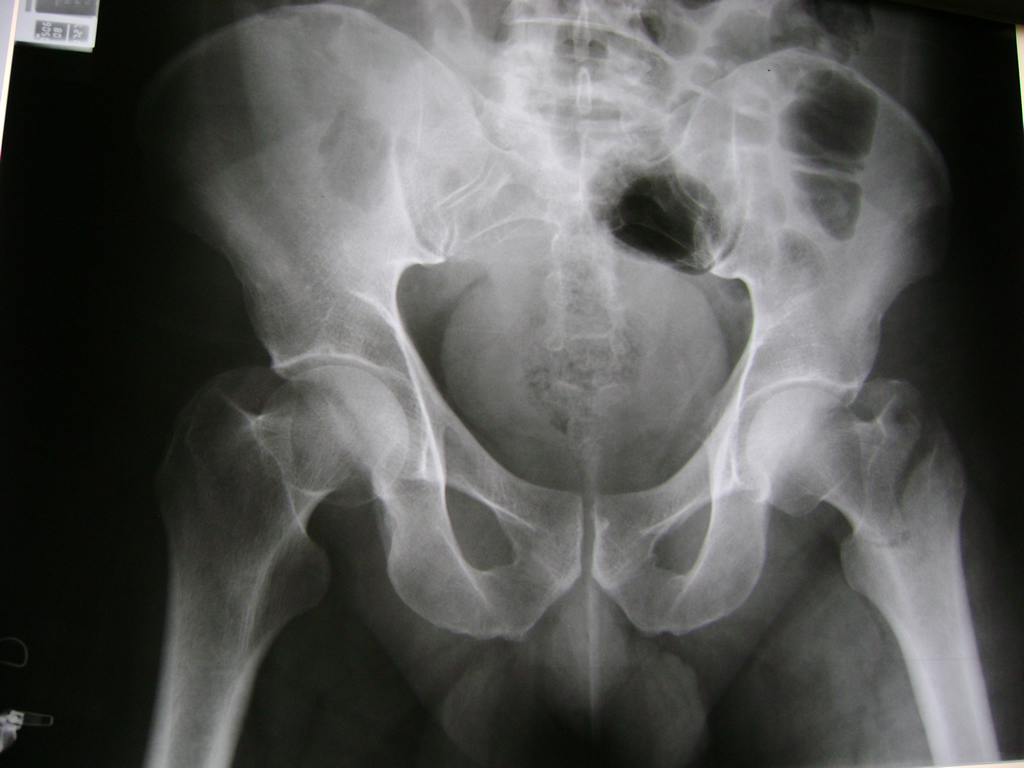

Cirugía de Fémur - Cadera

La cirugía de fractura de cadera se realiza para reparar una ruptura en la parte superior del hueso del muslo. Este hueso se denomina fémur.

Es parte de la articulación coxofemoral. Si una fractura de cadera no recibe tratamiento, es posible que deba permanecer en una silla o en la cama.